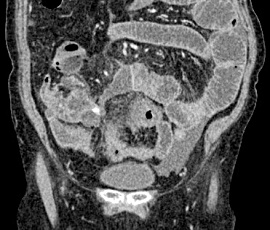

右下腹部痛にて受診。精査の結果、急性虫垂炎、汎発性腹膜炎と診断。手術(腹腔鏡下回盲部切除術、腹腔内ドレナージ術)を施行した。

CT画像